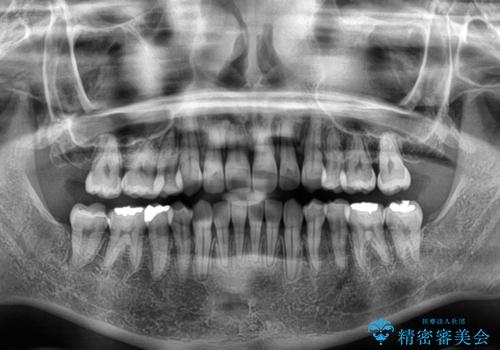

八重歯を改善 ワイヤー装置での抜歯矯正

八重歯をスムーズに解消するために、補助装置を用いることで速やかに歯列を整えることができました。

- 1年11ヶ月